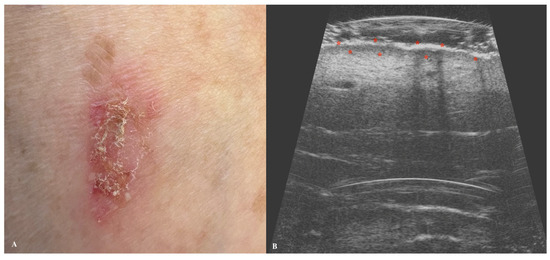

3. Squamous Cell Carcinoma

| Squamous Cell Carcinoma | Hypoechogenic lesion with irregular, poorly defined margins. Epidermal detachment and ulceration are common. More vascularized than BCC. |